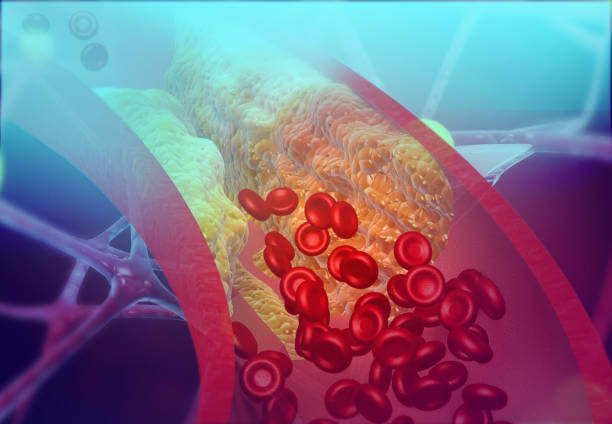

손상된 동맥 벽에 지방과 칼슘이 쌓여 혈관 내부에 플라크(동맥 벽의 지방 침착물)가 형성됩니다. 협심증과 관련된 지질 쌓임은 주로 혈액 속에 존재하는 지방인 콜레스테롤입니다. 콜레스테롤은 우리 몸에서 필요한 물질이지만, 과다하게 쌓이면 문제가 될 수 있습니다.

콜레스테롤은 혈액 속에서 지방의 형태로 존재하며, 우리 몸의 세포 구조와 기능을 유지하는 데 필요합니다. 하지만 고지방 식품을 섭취하거나 유전적인 요인으로 인해 콜레스테롤 수치가 높아지면, 혈관 벽에 콜레스테롤이 쌓이는 현상이 발생할 수 있습니다.

콜레스테롤이 혈관 벽에 쌓이면 "플라크" 라고 불리는 지방 침착물이 형성됩니다. 이 플라크는 동맥 벽 내부를 좁게 만들어 혈액 흐름을 제한합니다. 협심증은 주로 심장에 산소와 영양분을 공급하는 관상동맥에서 발생하므로, 관상동맥에 플라크가 형성되면 심장에 충분한 혈류가 공급되지 못해 협심증 증상이 발생할 수 있습니다.